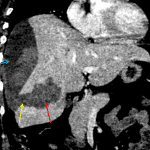

- Intermediate attenuation right hepatic subcapsular collection measuring 14 x 5 x 16 cm, which is in continuity with an intrahepatic collection with similar imaging characteristics in the inferior aspect of the right hepatic lobe measuring 6 x 6 x 7 cm

- Ill-defined hyperenhancing hepatic lesions in segments 5 and 8, with enhancing soft tissue extending along the periphery of the intrahepatic collection

- Ruptured hepatic adenoma

Large hepatic subcapsular hematoma measuring 14 x 5 x 16 cm, which is in continuity with an intrahepatic hematoma in the inferior aspect of the right hepatic lobe measuring 6 x 6 x 7 cm. Adjacent to the parenchymal hematoma, there are ill-defined hyperenhancing hepatic lesions in segments 5 and 8, which are favored to represent adenomas in the absence of history of malignancy and are the likely source for hemorrhage. Recommend surgical evaluation and followup liver protocol MRI for further assessment.